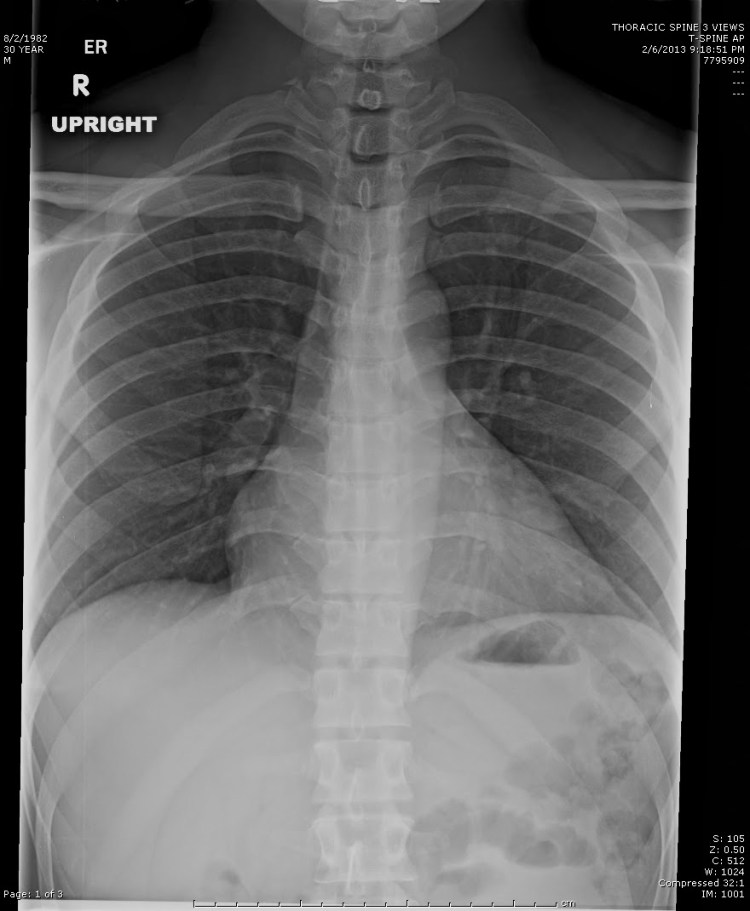

Visión Integral de la Anatomía Pulmonar: Tele de Tórax en Detalle

La tele de tórax proporciona una visión integral de la anatomía pulmonar. Permite evaluar la forma y el tamaño de los pulmones, identificar posibles masas o nódulos, y detectar la presencia de líquidos o aire en la cavidad pleural. Esta información es esencial para el diagnóstico y seguimiento de diversas enfermedades respiratorias.

La tele de tórax es particularmente útil en la identificación de infecciones pulmonares. Puede revelar patrones característicos asociados con neumonías, bronquitis y otras infecciones respiratorias. La detección temprana de estas condiciones es crucial para iniciar el tratamiento adecuado y prevenir complicaciones.

Además, la tele de tórax permite un diagnóstico más profundo de enfermedades pulmonares intersticiales, que afectan el tejido conectivo de los pulmones. Puede revelar fibrosis pulmonar, sarcoidosis u otras condiciones que afectan la estructura del tejido pulmonar. Este nivel de detalle es esencial para planificar el tratamiento y monitorear la progresión de la enfermedad.

La tele de tórax también juega un papel crucial en la detección temprana de tumores pulmonares. Puede revelar la presencia de masas o nódulos que podrían indicar la presencia de cáncer de pulmón. La identificación temprana es clave para aumentar las tasas de supervivencia y facilitar intervenciones médicas oportunas.